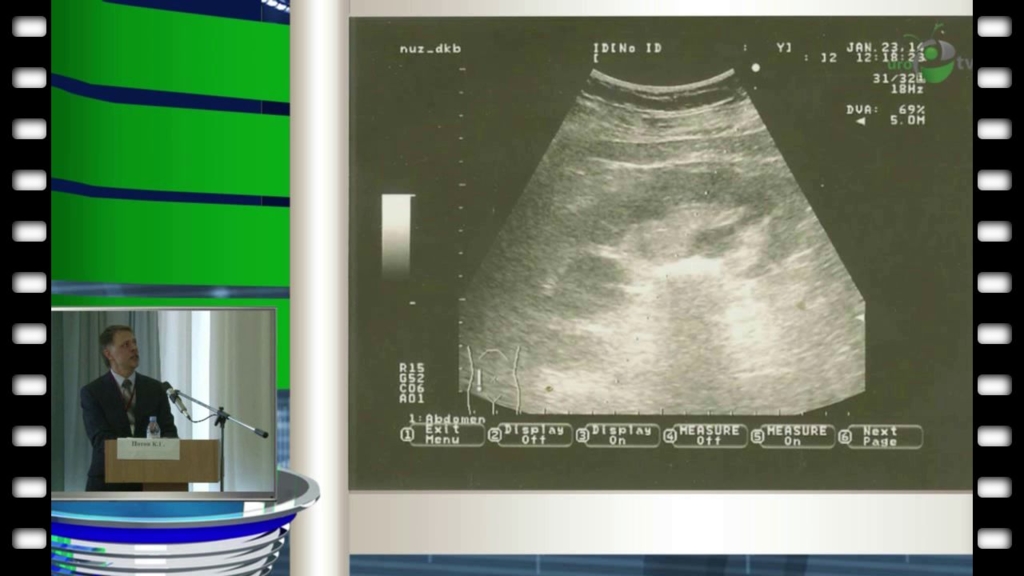

Нотов К.Г. - "Перкутанная нефролитолапаксия в сочетании с лазерной эндотомией"